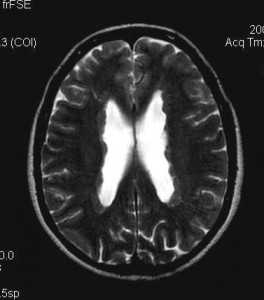

Томограммы метахроматической лейкодистрофии

Заболевание проявляется в возрасте от 1 года до 30 лет (1-4 года - инфантильная форма, 5-20 лет - ювенильная форма, позже 20 лет - взрослая форма). Нарастает мышечный тонус, нарушается координация движений, изменяется походка. Появляются глазодвигательные расстройства, дизартрия, снижаются сухожильные рефлексы. Грубо нарушается психическое развитие, могут быть судорожные припадки. В далеко зашедшей стадии (через несколько лет) развиваются тетраплегия, децеребрационная ригидность, декортикация, грубые псевдобульбарные и бульбарные нарушения. На КТ головного мозга обнаруживают симметричные очаги пониженной плотности в белом веществе лобных и теменных долей мозга. В мозге выявляется почти полная демиелинизация с дегенерацией демиелинизированных волокон, особенно выраженная в каудальной части мозгового ствола. Смерть наступает через 2-10 лет после начала заболевания.